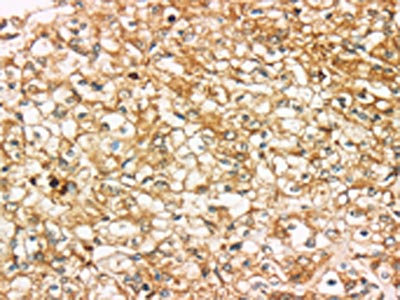

The image on the left is immunohistochemistry of paraffin-embedded Human tonsil tissue using CSB-PA975446(SIGLEC15 Antibody) at dilution 1/35, on the right is treated with synthetic peptide. (Original magnification: ×200)

The image on the left is immunohistochemistry of paraffin-embedded Human prostate cancer tissue using CSB-PA975446(SIGLEC15 Antibody) at dilution 1/35, on the right is treated with synthetic peptide. (Original magnification: ×200)el: 12%SDS-PAGE, Lysate: 60 μg, Lane: Mouse bladder tissue, Primary antibody: CSB-PA975446(SIGLEC15 Antibody) at dilution 1/200, Secondary antibody: Goat anti rabbit IgG at 1/8000 dilution, Exposure time: 5 seconds